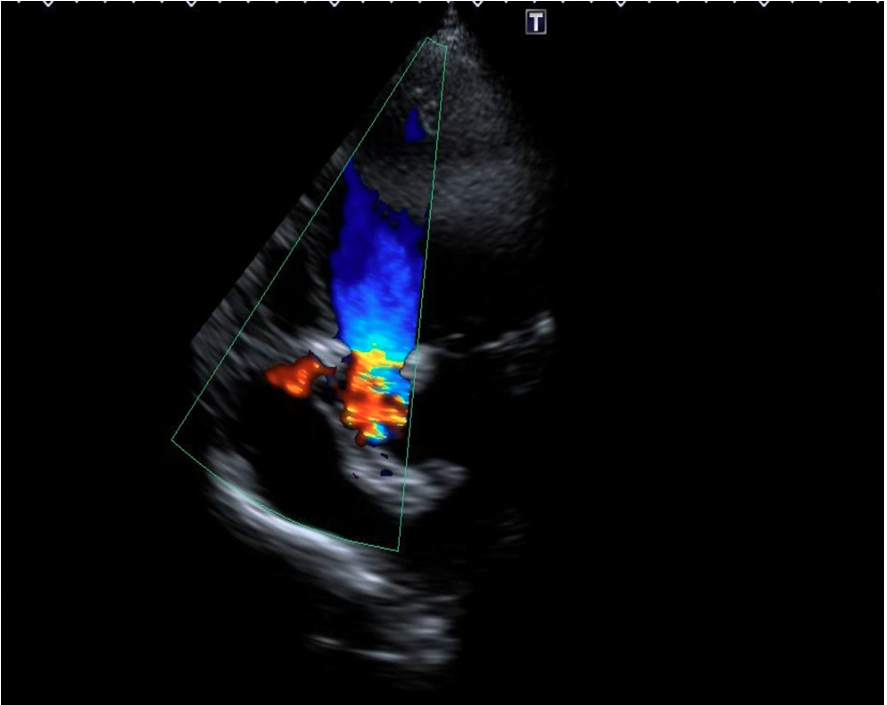

We chose an appropriately sized occluder, which was 20% greater than the entrance diameter of the ruptured SVA. The selected occluder with its attached delivery cable was inserted through the delivery sheath from the venous route, and its aortic disc was deployed in the ascending aorta. Positioning of the device (an ADO single-disc device of 6-8 mm) was then confirmed under transthoracic echocardiography (Figures 4A-C, Videos 4A-C).

Figure 4. (A) Positioning of the Amplatzer Duct Occluder (ADO) device (Abbott) (blue arrow). (B) Transthoracic echocardiography. (C) No residual shunt observed across the defect following device placement on transthoracic echocardiography.

(Figure 4A)

(Figure 4B)

(Figure 4C)